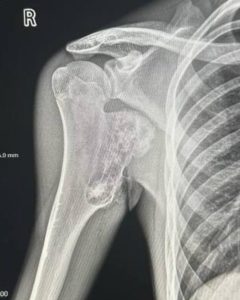

Клінічний випадок. Пацієнт звернувся до нас зі скаргами на утворення у верхній третині плеча, яке заважало притиснути руку до тулуба,...